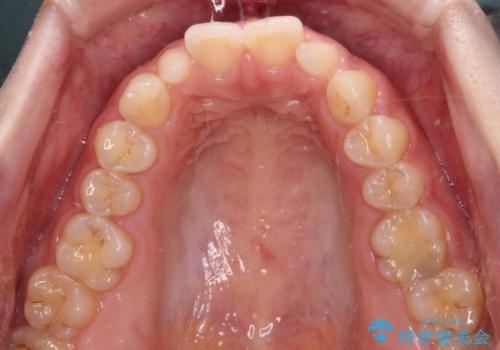

- 前歯の矮小歯と捻れや変色を気にして来院された患者様です。

結婚式が近いということもあり、前歯4本をオールセラミッククラウンにて補綴治療することとしました。

前歯の捻れは、オールセラミッククラウンよりも矯正治療による改善の方が、歯を削らなくて済むためお勧めとなります。

しかし、矮小歯の改善はオールセラミッククラウンでの補綴治療が必要であり、幅径のバランスを取る必要があるため、4前歯の補綴治療を選択しました。